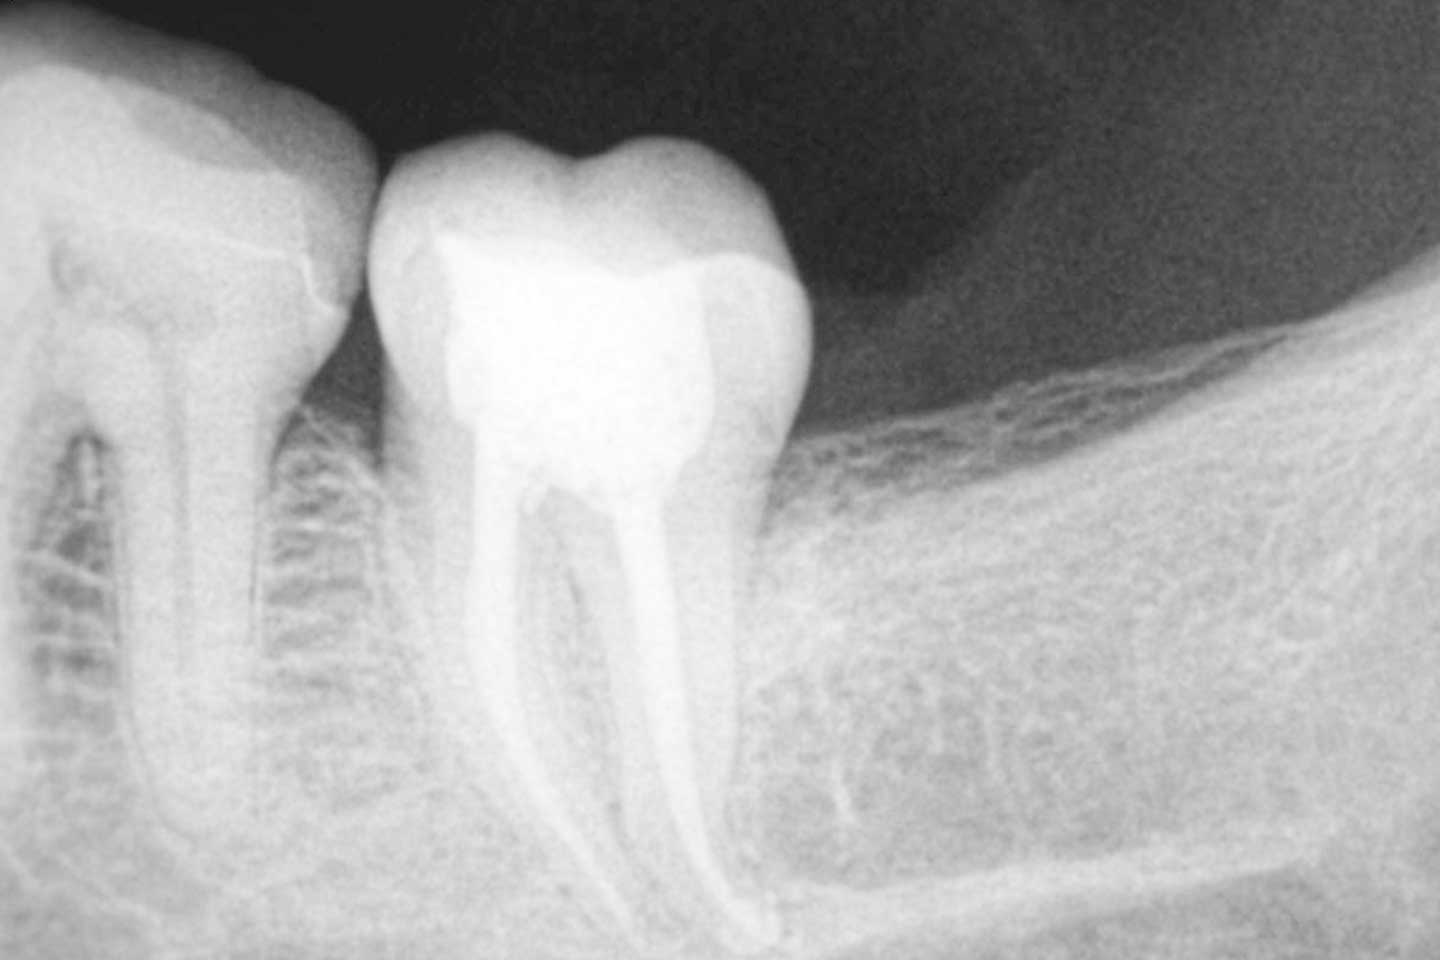

La endodoncia es una intervención que se realiza para intentar conservar un diente que de otra manera tendría que ser extraído. Esta especialidad dental, consiste en la eliminación del tejido pulpar (“nervio”), que está dentro de las raíces dentarias, y de esta manera mantener el diente y su función masticatoria.

Con el objetivo de mejorar la calidad de nuestros tratamientos de endodoncia hemos incorporado localizadores electrónicos de ápices, endodoncia rotatoria, obturación termoplástica y sistemas de irrigación. Todo esto hace que el resultado de las endodoncias sea excelente.